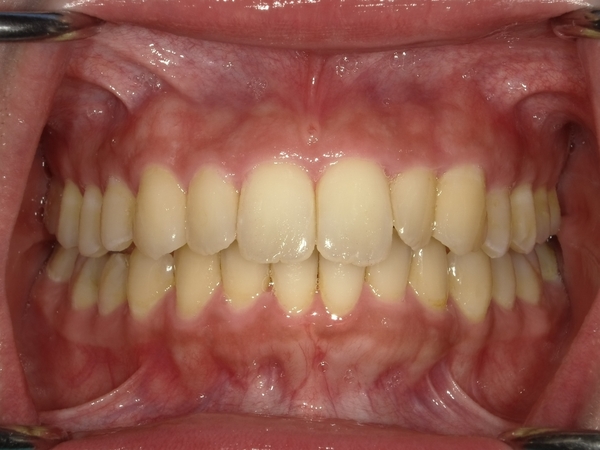

ガタガタとした歯並びや八重歯(叢生)CASE53